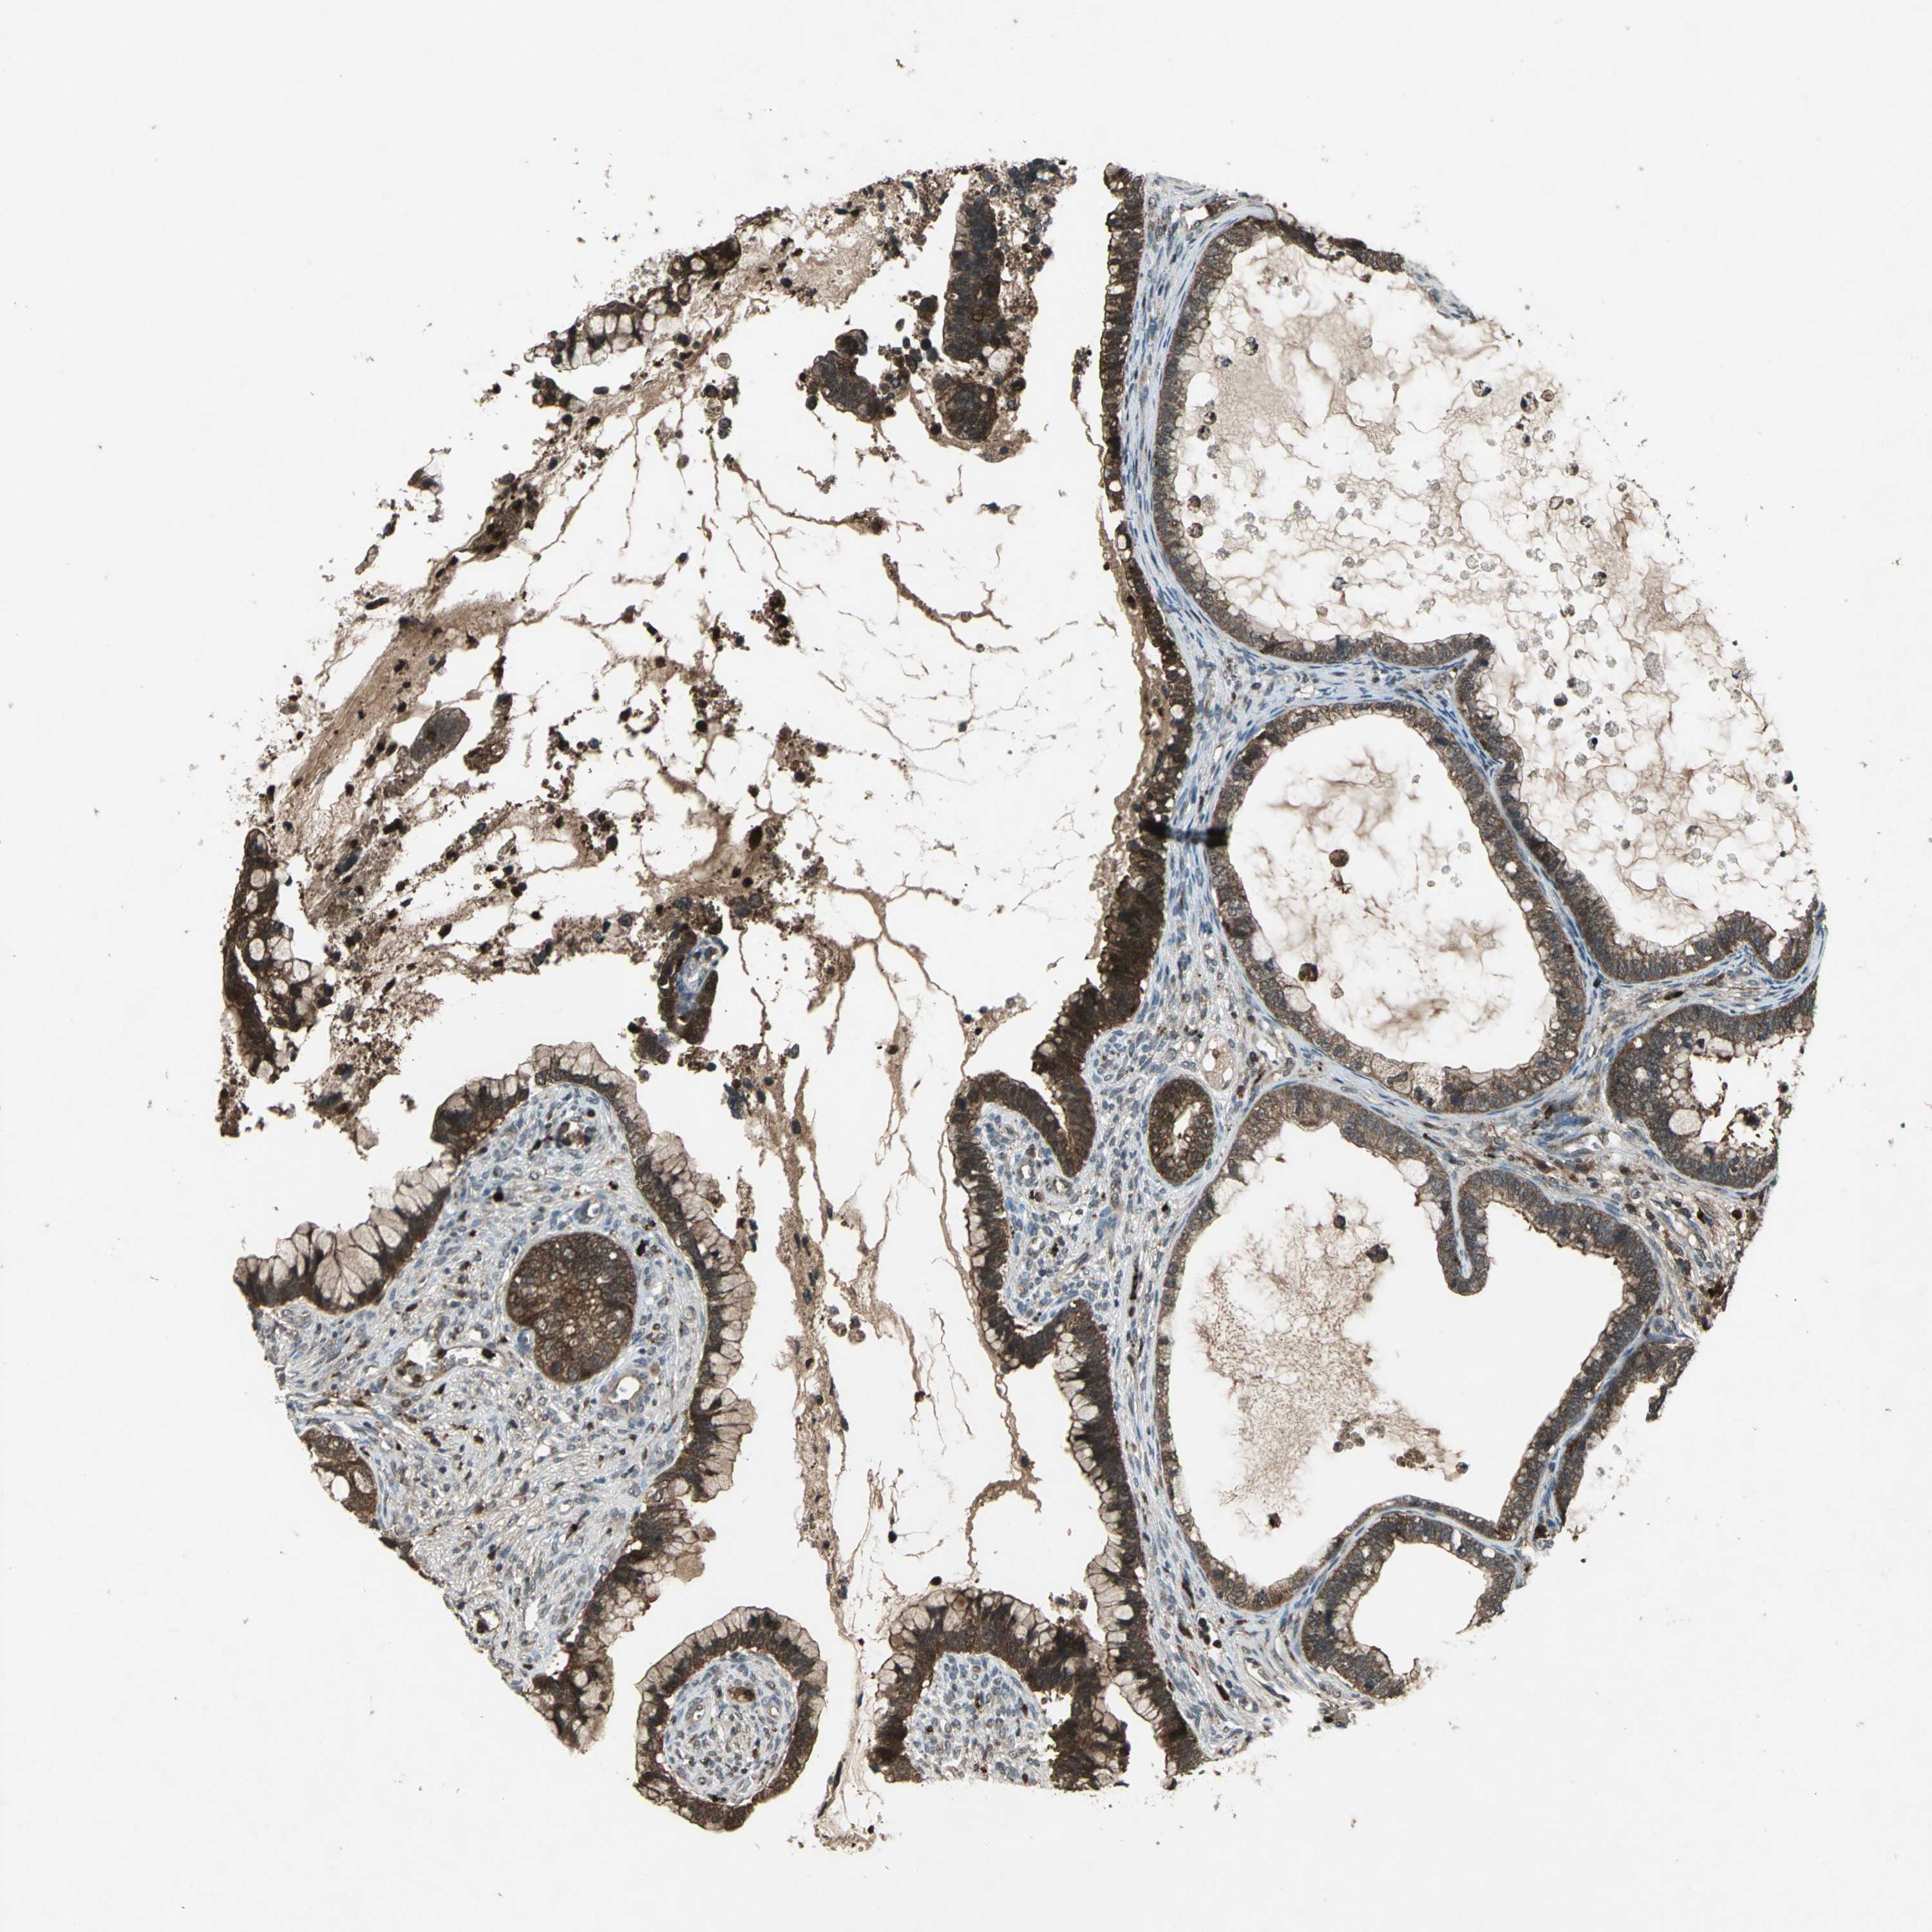

CERVICAL CANCER - Protein expressioni

A mouse-over function shows sample information and annotation data. Click on an image to view it in a full screen mode. Samples can be filtered based on level of antibody staining by selecting one or several of the following categories: high, medium, low and not detected. The assay and annotation is described here.

Note that samples used for immunohistochemistry by the Human Protein Atlas do not correspond to samples in the TCGA dataset.

Antibody stainingi

Antibody staining in the annotated cell types in the current human tissue is reported as not detected, low, medium, or high, based on conventional immunohistochemistry profiling in selected tissues. This score is based on the combination of the staining intensity and fraction of stained cells.

Each image is clickable and will lead to virtual microscopy that enables deeper exploration of all samples and also displays staining intensity scores, fraction scores and subcellular localization as well as patient and tissue information for each sample.

Antibody HPA049074

Antibody HPA054496

Antibody CAB006853

Antibody CAB015948

Staining

High

Medium

Low

Not detected

Intensity

Strong

Moderate

Weak

Negative

Quantity

>75%

75%-25%

<25%

None

Location

Nuclear

Cytoplasmic/membranous

Cytoplasmic/membranous,nuclear

Squamous cell carcinoma, NOS

Adenocarcinoma, NOS